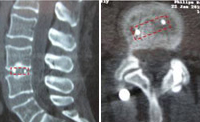

Izquierda: escáner de control post-operatorio de la caja intersomática PEEK

colocada por técnica percutánea. Derecha: doble fusión intervertebral con caja

de PEEK con incisiones de solo 12 mm y bajo anestesia local